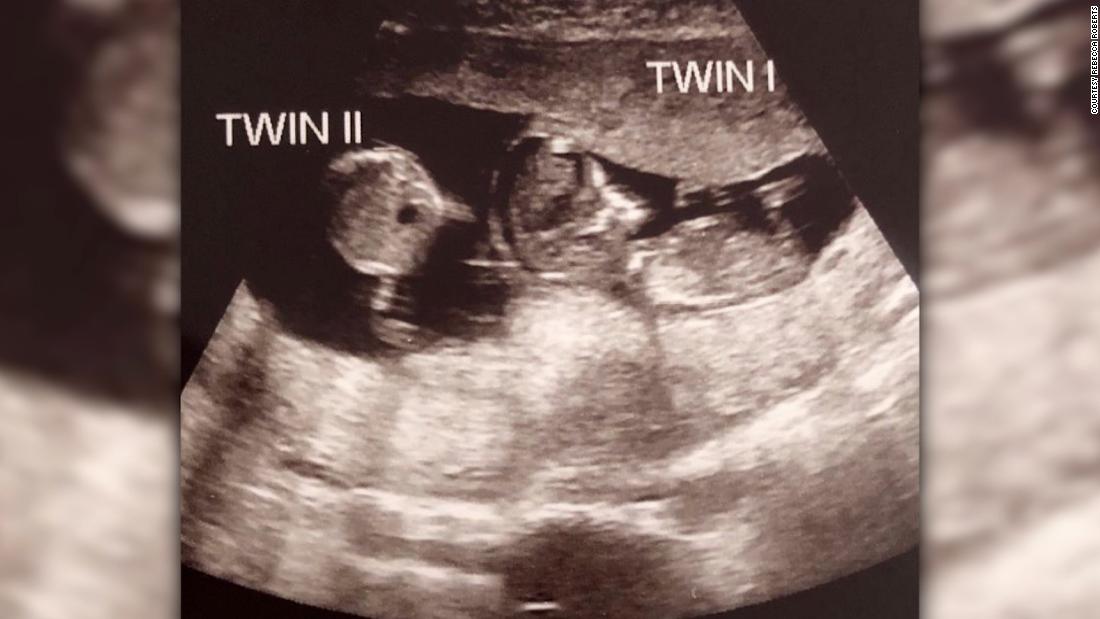

Kết quả siêu âm ở tuần thứ 7 và thứ 10 cho thấy Noah (tên của em bé thứ nhất) phát triển bình thường trong bụng mẹ và không hề có dấu hiệu của "sự sống thứ hai". Tuy nhiên, lần siêu âm ở tuần tuổi thứ 12 của Noah cho thấy có một bào thai mới được hình thành. Đó là Rosalie, em song sinh của Noah.

Hình ảnh siêu âm thai kỳ của Rebecca và sự xuất hiện của bào thai thứ hai. Ảnh: CNN